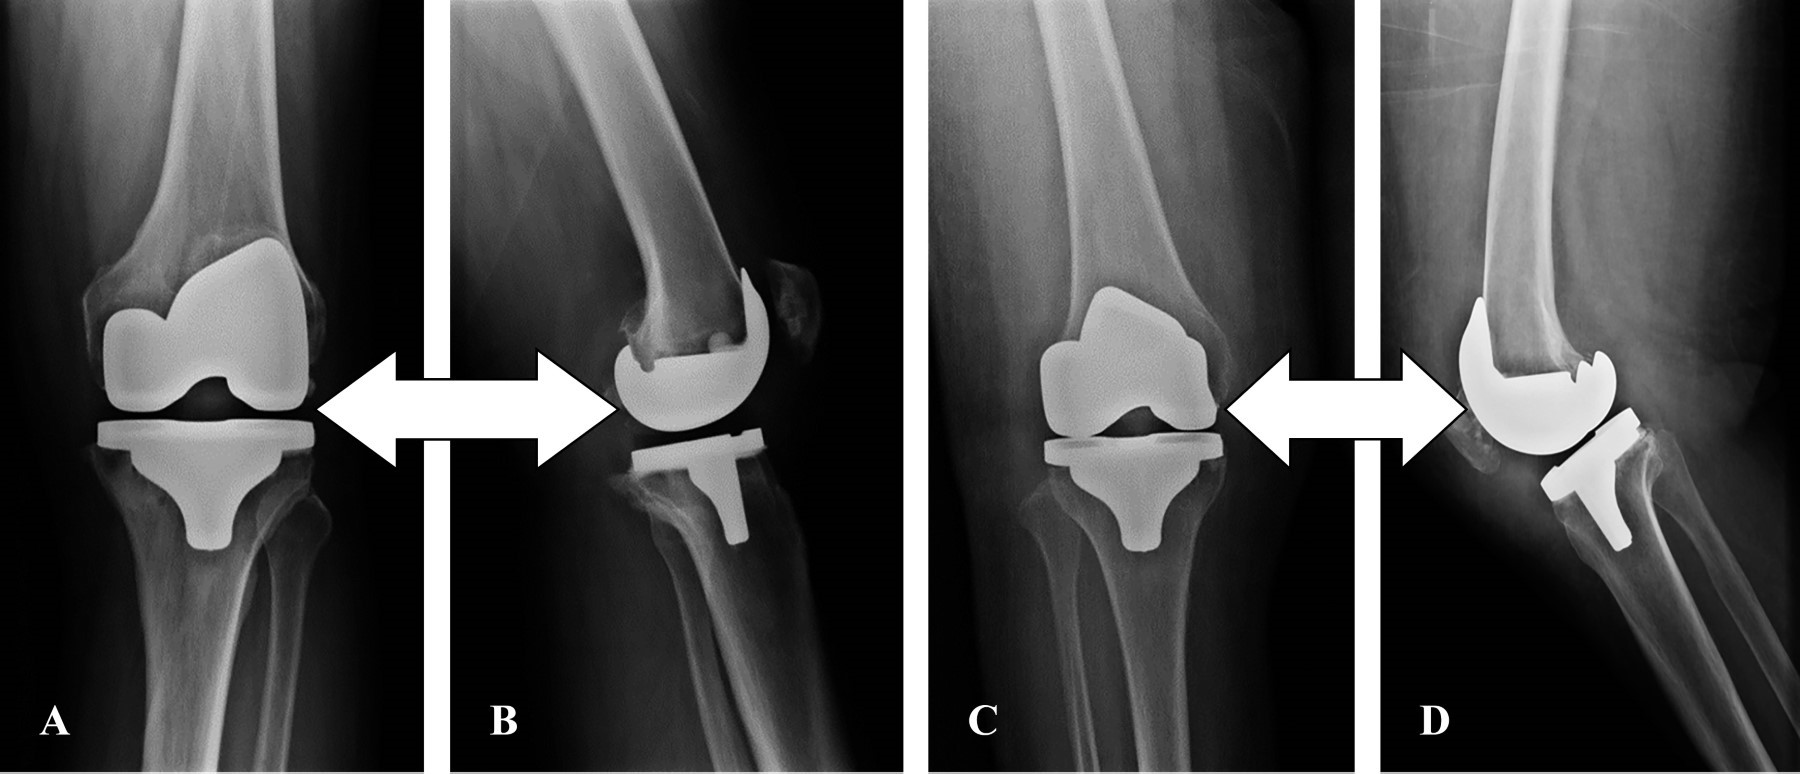

El tipo de prótesis que se utilizó en este estudio fue la posteroestabilizada (Figura 7).

Figura 7